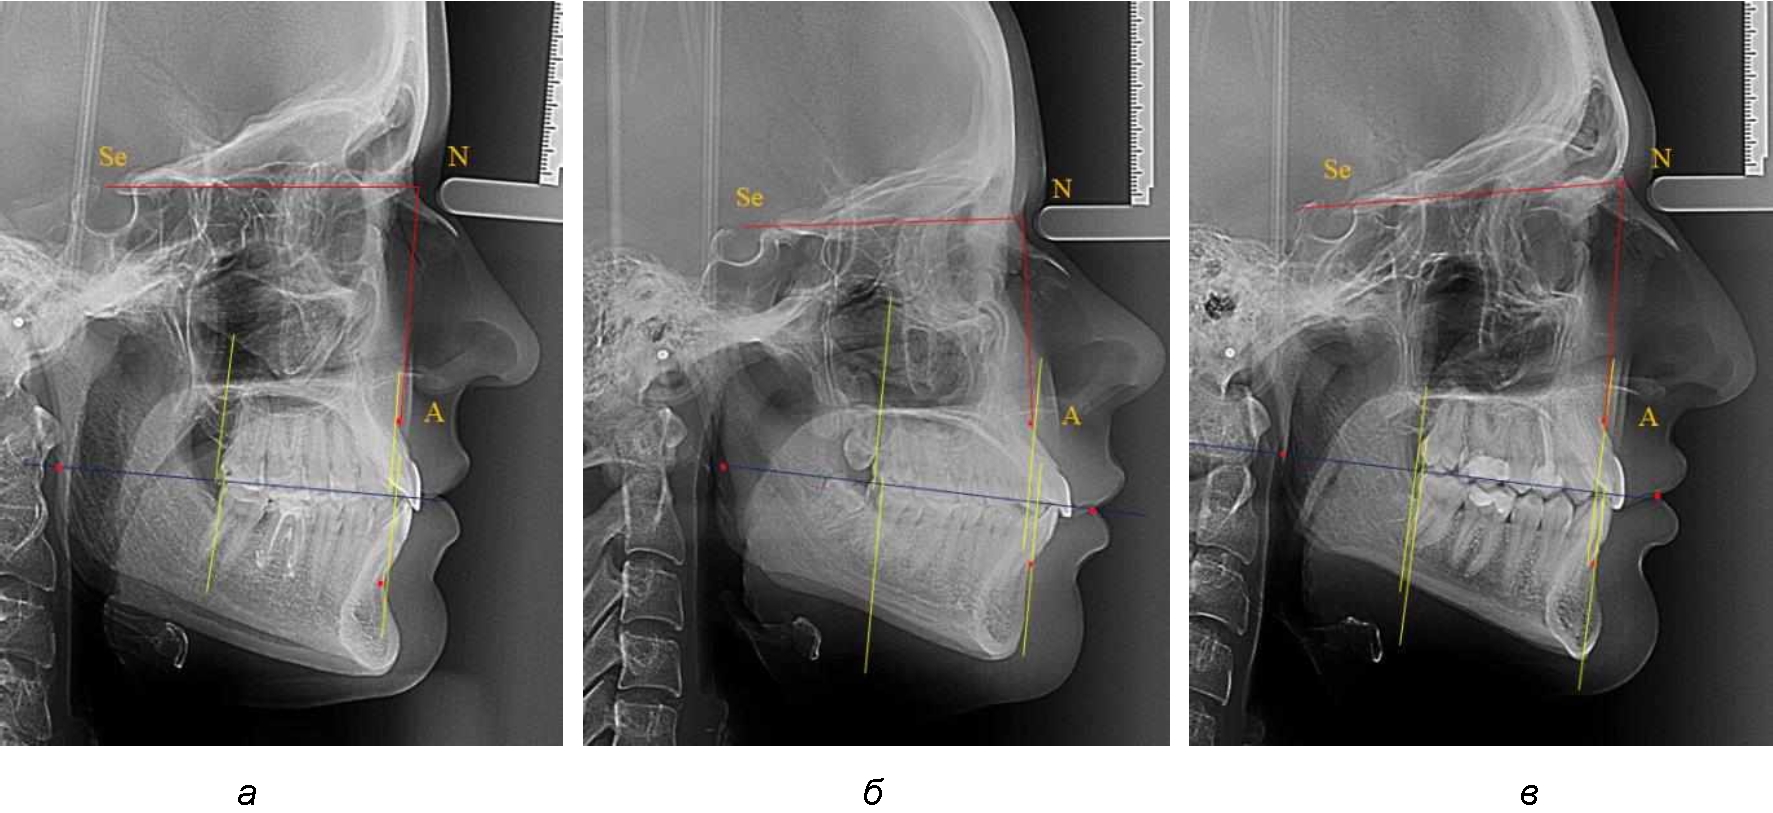

При анализе рентгенограмм, было отмечено, что на 26 снимках из 58 [(44,83 ± 6,53) %] отмечалась нормопозиция верхней челюсти. При этом средняя величина лицевого угла (ANSe) составила (85,04 ± 0,56)°, и пациенты были отнесены к 1-й группе 1-й подгруппе. Антепозиция верхней челюсти была отмечена на 20 те-лерентгенограммах [(34,483 ± 6,24) %], при этом величина лицевого угла составляла (89,12 ± 0,62)°. Ретропозиция была отмечена на 12 рентгенограммах [(20,69 ± 5,32) %], а средняя величина лицевого угла составляла (80,21 ± 0,48)°.

При всех вариантах положения верхней челюсти, было отмечено, что альвеолярно-денталь-ные размеры верхних зубо-челюстных дуг были близки по значению к аналогичным размерам нижней челюсти и разница в размерах не превышала 1,0–1,5 мм, а средняя величина различия показателей составляла (1,07 ± 0,54) мм.

Расстояние от конструируемой точки окклюзионной плоскости на ветви челюсти («rmРOcP») до апикальных точек Downs на обеих челюстях также коррелировало между собой, и средняя величина различия показателей составляла (1,23 ± 0,69) мм. Проекция нижней апикальной точки на окклюзионную линию, как правило, располагалась несколько кпереди проекции верхней апикальной точки, на величину около 1 мм, что соответствовало оптимальным данным Wits-анализа.

Аналогичное расстояние было отмечено и при расположении дистальных окклюзионных точек верхней и нижней челюсти (рис. 2).

Рис. 2. Положение апикальных точек и челюстей при нормопозиции (а), антепозиции (б) и ретропозиции (в) верхней челюсти